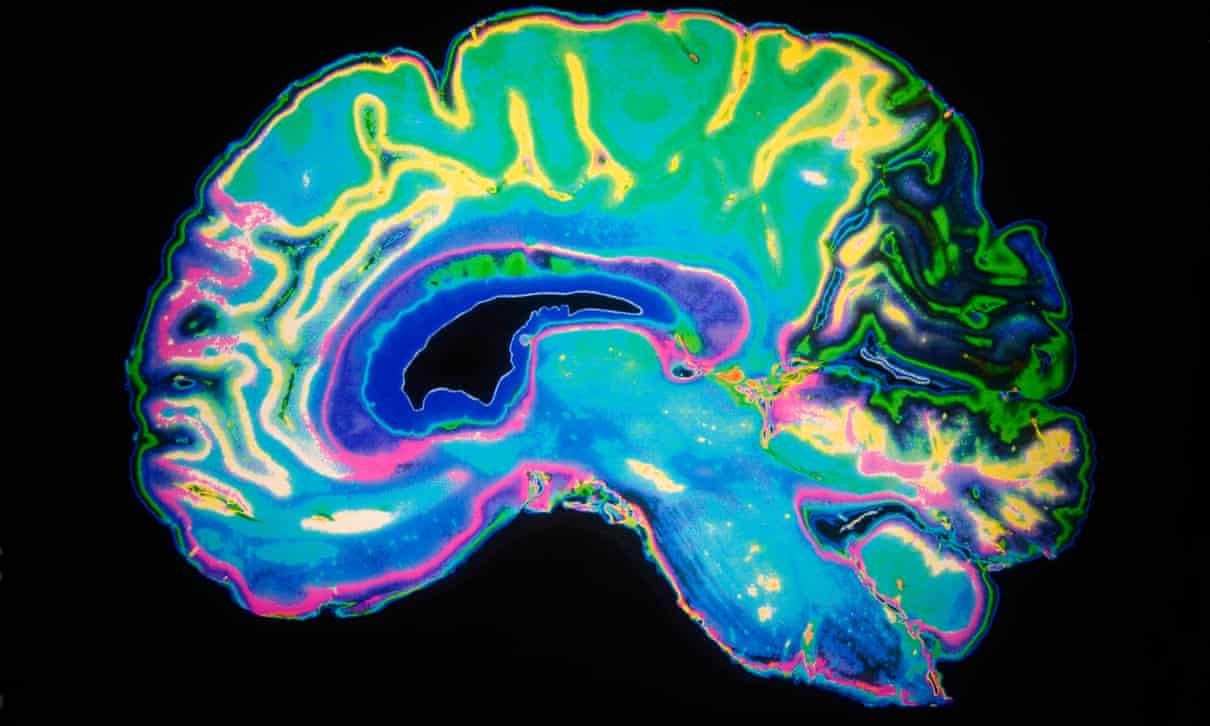

Neurologii au oferit detalii despre peste 40 de pacienți infectati cu virusul Covid-19 din Marea Britanie ale căror complicații variau de la inflamația creierului și delir la leziuni nervoase și accident vascular cerebral . În unele cazuri, problema neurologică a fost primul și principalul simptom al pacientului.

O duzină de pacienți aveau inflamații ale sistemului nervos central, 10 aveau boli ale creierului cu delir sau psihoză, opt aveau accidente vasculare cerebrale și alți opt aveau probleme nervoase periferice, în mare parte diagnosticate ca sindromul Guillain-Barré, o reacție imună care atacă nervii și provoacă paralizie. Este fatal în 5% din cazurile diagnosticate astfel, deci nu de speriat dar de luat in considerare la aprecierea gravitatii cazului.

Gama completă de afecțiuni ale creierului cauzată de Covid-19 este posibil să nu fi fost preluată încă, deoarece mulți pacienți din spitale sunt prea bolnavi pentru a examina scanerele cerebrale sau cu alte proceduri. „Ceea ce avem nevoie acum este o cercetare mai bună pentru a privi ceea ce se întâmplă cu adevărat în creier”, a spus dr Zandi.